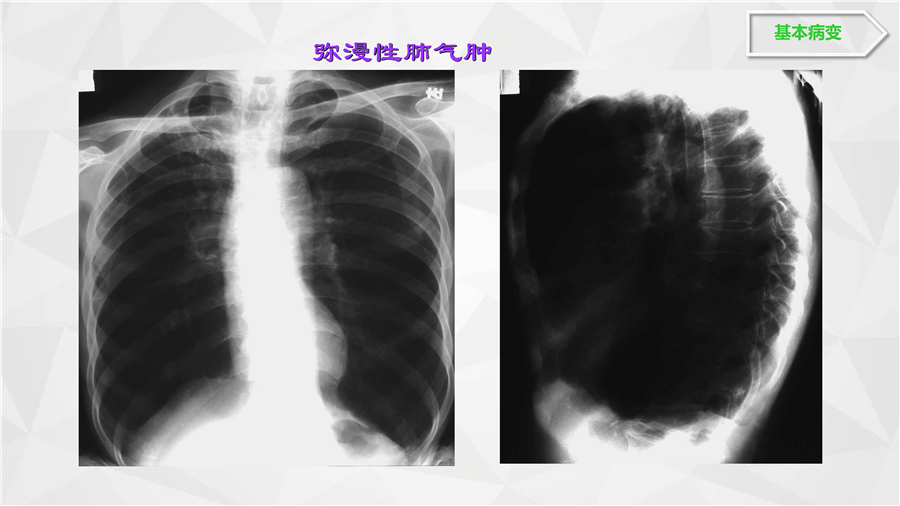

呼吸系统二